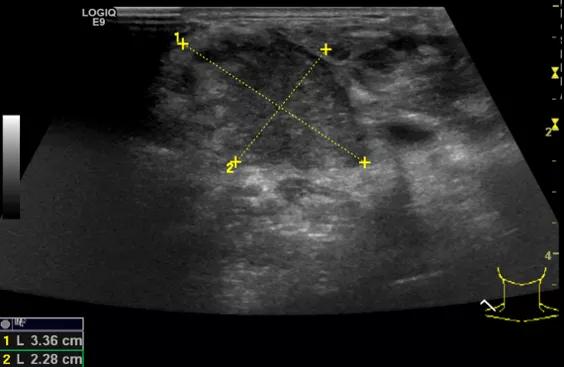

随后,徐栋教授进一步分享了五个临床实战病例,带来了更直观的热消融治疗经验。第一个病例是62岁肺癌患者,术后1年余发现双侧锁骨上淋巴结复发,侵犯神经,存在静脉回流、淋巴回流障碍,肿胀、疼痛非常明显。影像显示患者淋巴结边界不清、形态不规则,存在浸润,血流强化增强。由于患者在系统治疗后进展,且主要目的缓解症状、减瘤。局麻下行热消融术,从后向前逐层消融,热消融之后超声造影即刻评估显示完全充盈缺损,完全覆盖病灶。

(病例1图例)